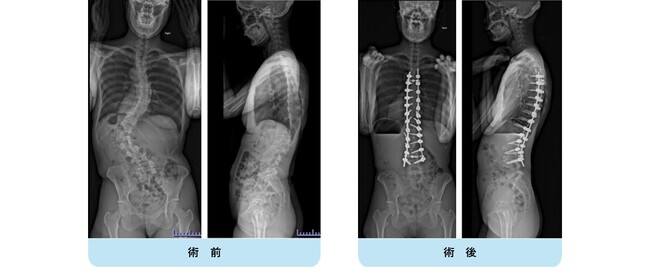

思春期特発性側弯症の全脊椎レントゲンで背骨が大きくSの字に曲がっています。最も曲がっている箇所は80°で、高度側弯に分類されます。後方からの脊柱側弯矯正術で真っ直ぐになっています。

また、側弯の患者さんは一般的にフラットバックと言って背骨の生理的後弯(背中の丸み)が失われています。この症例も胸椎後弯角は5°で典型的なフラットバックを呈しています(正常は20°~30°程度です)。この影響は頸椎の形態にも影響を及ぼし、この症例も頸椎が既に後弯(正常は前弯)しています。(黄色矢印)

ストレートネックという頸椎の前弯が消失して頸部の愁訴が出現する病態は広く知られていますが、更に変形が進行した頸椎と考えて下さい。

以前はこのフラットバック(生理的胸椎後弯の消失)を治すことは困難でしたが、当院では手術方法の様々な工夫により生理的胸椎後弯の復元を行っております。この症例は術後に胸椎後弯角が26°と改善しており、生理的な胸椎後弯が形成されています。さらに頸椎後弯にも良い影響を及ぼし、術後は頸椎前弯化が得られつつあるのが分かります。(黄色矢印)

他、側弯変形は必ず大なり小なりの回旋変形を伴います。脊柱の回旋変形は胸郭(肋骨)の回旋につながり、これにより側弯の患者さんは背中の片方が出っ張っています(多くは右)。リブハンプと言いますが、脊柱変形矯正によりこの回旋変形も改善します。この症例も術前に肋骨がかなり隆起していますが、術後にこの隆起がかなり減じているのが分かります。(赤矢印)